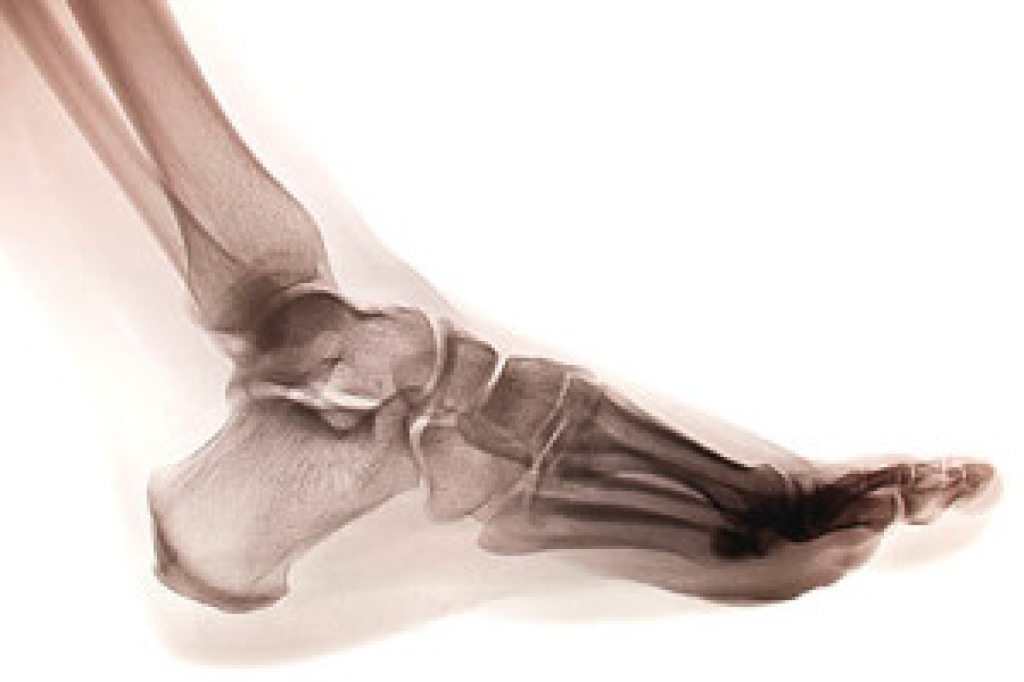

Since your feet are what support your entire weight when standing, any additional weight can result in pain and swelling. Being overweight is one of the main contributors to foot complications.

Extra Weight – Even putting on just a few extra pounds could create serious complications for your feet. As your weight increases, your balance and body will shift, creating new stresses on your feet. This uneven weight distribution can cause pain, even while doing the simplest tasks, such as walking.

Plantar fasciitis – Pressure and stress that is placed on muscles, joints, and tendons can trigger plantar fasciitis, which is an inflammation of tissue that forms along the bottom of the foot.